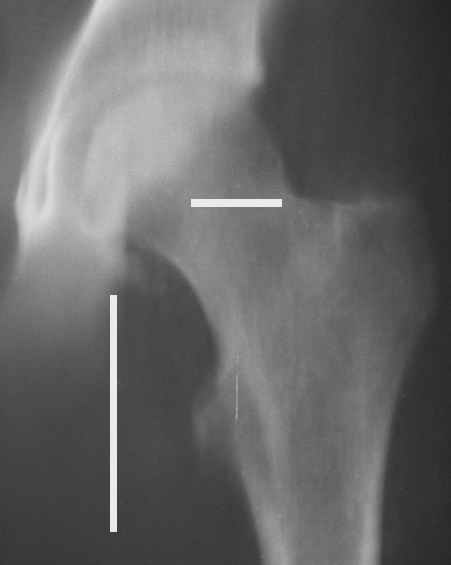

Уважаемые коллеги! Заканчивая обследование больного с переломо-вывихом бедра сделал ему обычные R-томограммы. Кажется удалось "поймать" и отломок и донорское место. Мои выводы - в скиаграмме. Считаю, что это передне-нижний фрагмент головки, образовавшийся вследствии отрывного перелома. На томограммах отломок обозначаю длинной стрелкой, а место откуда он оторвался - более короткой. Учитывая тот факт, что его размеры по КТ 25 х 15 мм считаю, что его фиксация на место необходима для профилактики артроза, что при 16-ти летнем возрасте пациента важно в плане максимального отодвигания эндопротезирования. Планирую оперировать его 24.05.05 г. Результаты представлю.

Прямой 19.05

Несколько соображений к "картинкам". На прямом снимке и КТ-томограммах все типичные линии вертлужной впадины: крыша, передняя стенка, задняя стенка - сохранены. На КТ-сканах 6 и 7 появляется фрагментация головки. С учетом R-томограмм отломок расположен спереди-снизу, а не сзади-сверху от сустава, как написано в описании КТ.